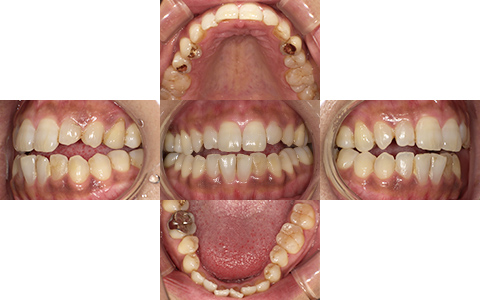

Before

After

| 施術内容 | 表側ワイヤー矯正 |

|---|---|

| 治療期間 | 8ヵ月 |

| 費用 | 770,000円+検査・診断料55,000円 |

| リスク・副作用 | ・治療の初期段階では痛みや不快感が生じやすくなりますが、1週間前後で慣れます。 ・歯の動き方には個人差があるため、予想された治療期間より長くなる場合があります。 ・装置の使用状況や通院頻度など、患者さまの協力が不可欠で治療の結果や期間に影響します。 |